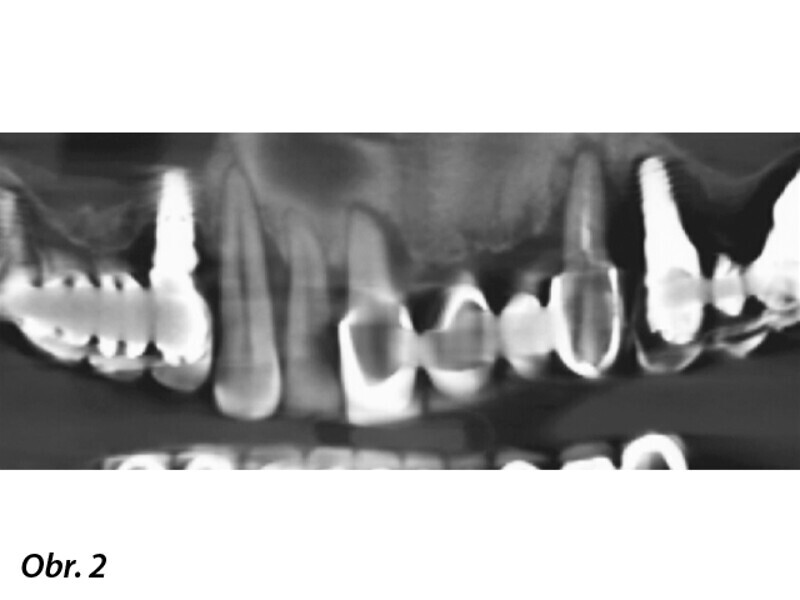

Kombinace standardních a ultrakrátkých implantátů při rehabilitaci celých úst